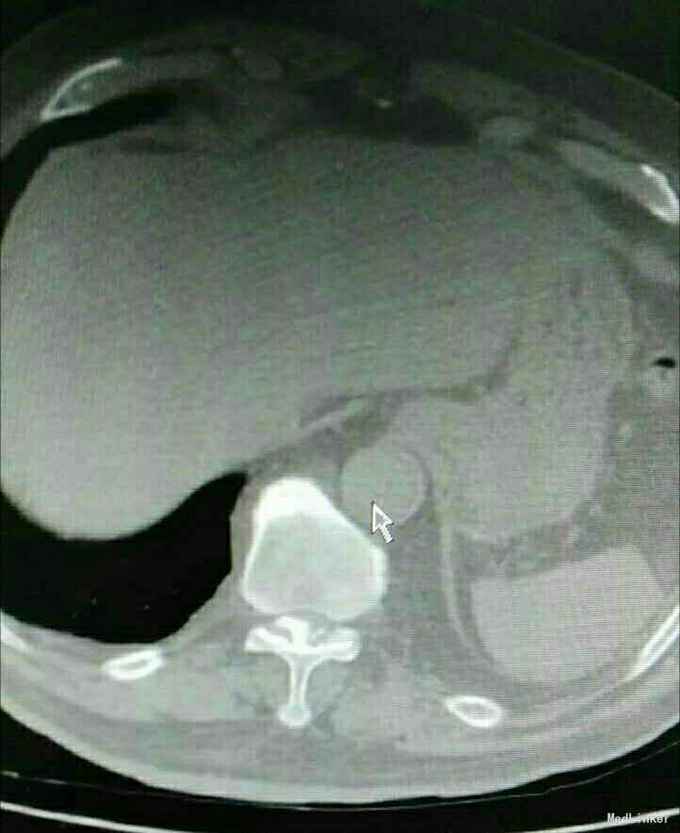

又是严重的胸椎黄韧带骨化,胸10-11、胸11-12。

渐进性双下肢感觉运动障碍10月,大小便障碍10天。